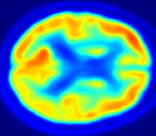

| MRI | PET | U-PET | U-PET (no att.) | pix2pix |

4.0.2 Qualitative Results

Looking at sample synthetic PET images in Fig. 3, it can be seen that all of the models are able to make reasonable predictions. The outputs of the U-PET and U-PET (no att.) look very similar and are smoothed compared to the input. The pix2pix predicts more details, which seem to be important for the discriminator. However, even though this model has finer predictions, the intensity values are worse compared to the U-PET and U-PET (no att.) as seen in Fig. 2; an example is given in Fig. 3 in the second row.

From a clinical perspective, the synthetic generated PET show a smoother version of the real PET images but keep the same pattern of FDG uptake, especially, hypometabolism in the respective brain areas. This backs up our hypothesis, that MRI contains information that correlates with the functional information of PET images. Moreover, the synthetic PET could be used as complementary visualization for physicians beyond the task of classification.